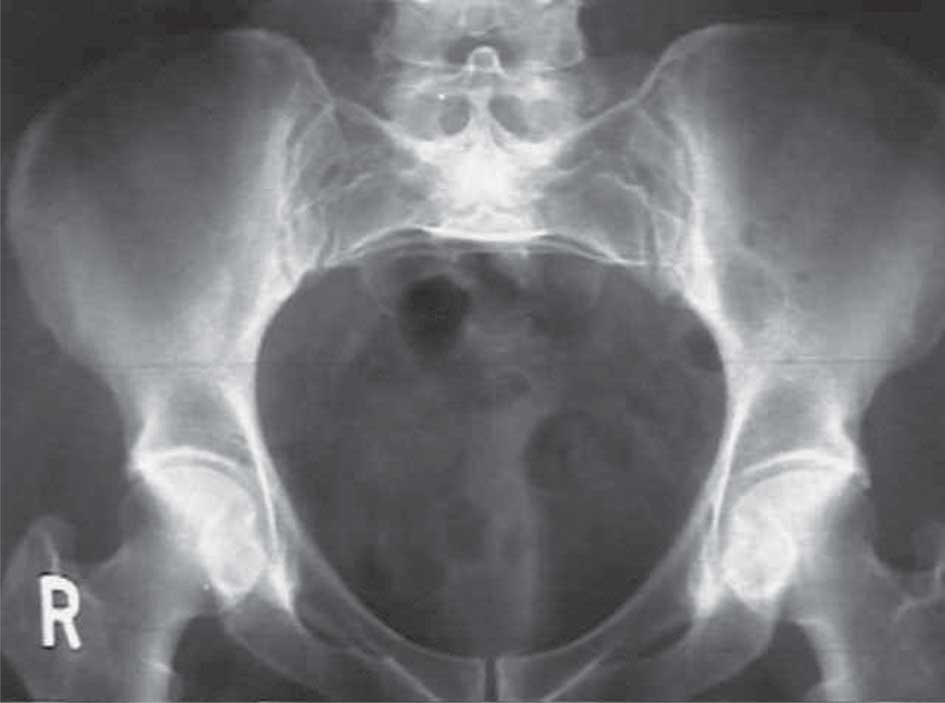

يتألف المسير التناسلي من حوض عظمي مشكل من عظام الحوض والجزء السفلي من العمود الفقري، ومن حوض رخو تشكله العضلات والأربطة، وتنجم أغلب عسرات الولادة الحوضية عن تضيق الحوض العظمي الذي يتوضع في مدخل الحوض inlet أو في وسطه midpelvis أو في مخرجه outlet.

1 ـ تضيق مدخل الحوض contraction of pelvic inlet:

يقال بوجود تضيق مدخل الحوض حين يكون القطر الأمامي الخلفي لهذا المدخل (القطر المفيد) أقل من 10سم أو يكون قطره المعترض أقل من 12سم، إضافة إلى أن شكل هذا المدخل يجب أن يكون من النموذج الأنثوي (بشكل القلب).

ويمكن قياس القطر المفيد بالمس المهبلي بقياس القطر الواصل من الخرشوم إلى الحافة السفلية لوصل العانة (القطر الخرشومي تحت العاني) وهو أطول من القطر المفيد (القطر الخرشومي خلف العاني) بـ 1.5سم، أما القطر المعترض فيقاس بالاستعانة بالصدى أو بالأشعة السينية.

| الشكل (1) منظر الحوض العظمي | الشكل (1) منظر الحوض العظمي | الشكل (3) مخرج الحوض |